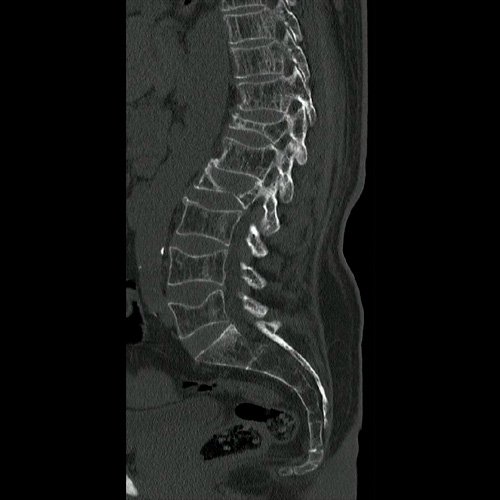

- Resonancia magnética de columna lumbar (28/08/2025): fractura aplastamiento de L2, a expensas de su platillo superior, que compromete el 60% de su altura. Fractura aplastamiento de L4 y L5, a expensas de platillos superiores, que afecta menos del 30% de la altura del cuerpo vertebral, sin desplazamiento. Estos cuerpos vertebrales presentan impronta de Schmorl en la placa terminal superior y resultan hiperintensos en STIR, hipointenso en T1, hallazgo compatible con edema óseo.

- Tomografía de columna lumbosacra (Día 0): Contamos con TC previa del día 04-09-2025 y RMI del día 28-08-2025. Hiperlordosis lumbar. Eje lumbar se encuentra desviado hacia la derecha. Persiste, de mayor jerarquía que en TC previa, la reducción de altura de los cuerpos vertebrales de D12, L2, mayor al 50%, con afectación del muro posterior. También se observa reducción del 30 % del cuerpo vertebral L4 y L5. Hallazgos en relación a fracturas aplastamiento patológicas. Además se observa marcada osteopenia generalizada. Disminución de la altura intervertebral de L2-L3 y L3-L4, a nivel de su margen posterior. Los demás espacios discales visualizados son de altura conservada. No se observan signos de protrusiones ni hernias discales. Ligera rarefacción del TCS paravertebral.